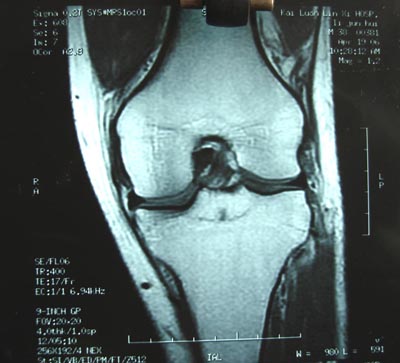

标题: 现将mri结果公布

手术证实是后交叉韧带胫骨附着处撕脱骨折。

术中用可吸收螺钉固定。